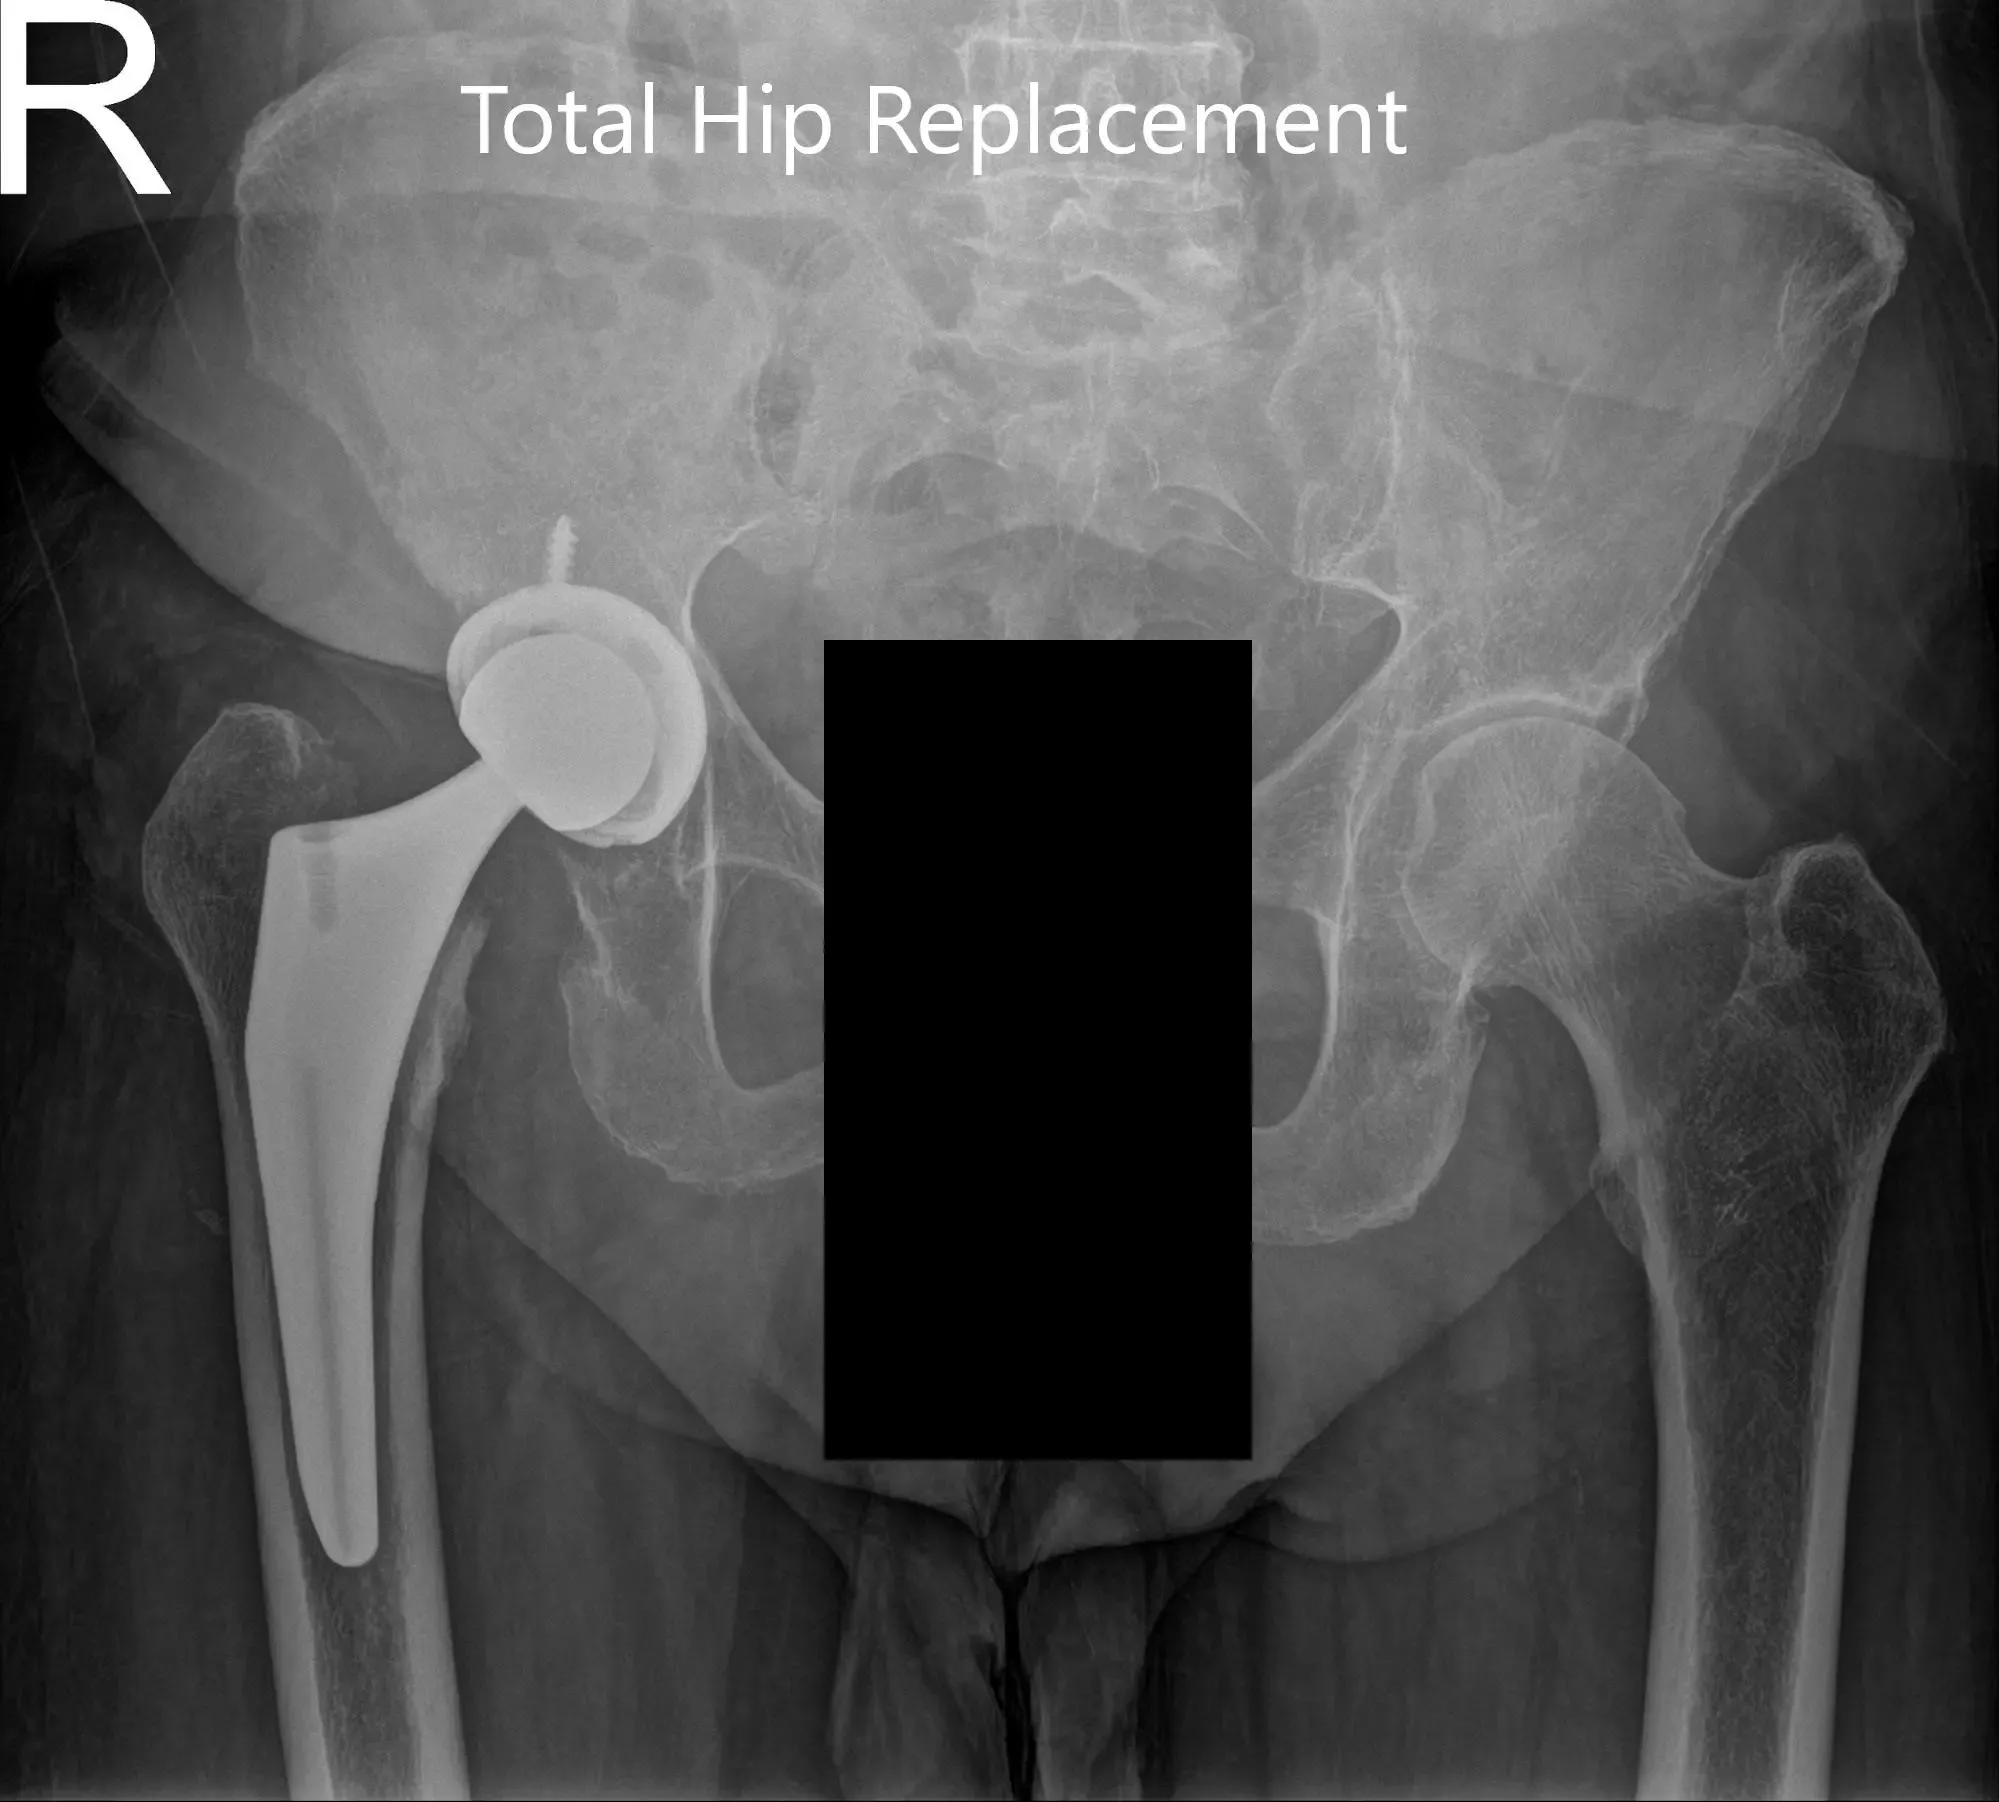

Postoperative X-ray showing the AP view of the pelvis and the frog-legged lateral view of the right hip

Postoperative X-ray showing the AP view of the pelvis and the frog-legged lateral view of the right hip (image-2)

Implants: Acetabular Shell 52 mm with 0-degree polyethylene insert 36 mm with a 6.5-mm screw with a 36-mm ceramic femoral head with a size 7, 127 degrees Femoral Prosthesis (114mm).